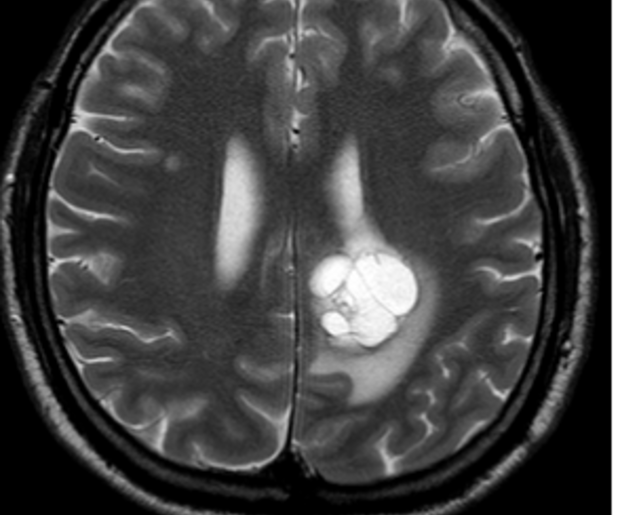

Do vaší ordinace vchází Milan Drahoš. Než se padesátiletý, velmi obézní muž dostane ode dveří k vámi nabízené židli, zadýchá se. Podle CT hrudníku, který si s sebou pacient přináší, má zvětšené uzliny v oblasti mediastina. Snímek odhaluje také mnohočetná ložiska plic. Není na co čekat, je třeba co nejrychleji zahájit léčbu. Ujmete se tohoto případu?